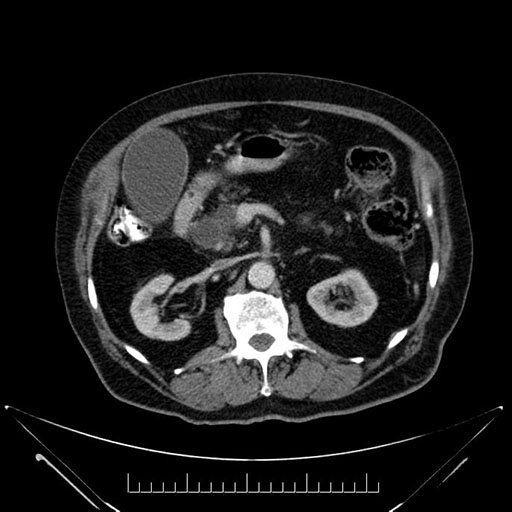

Axial - stented